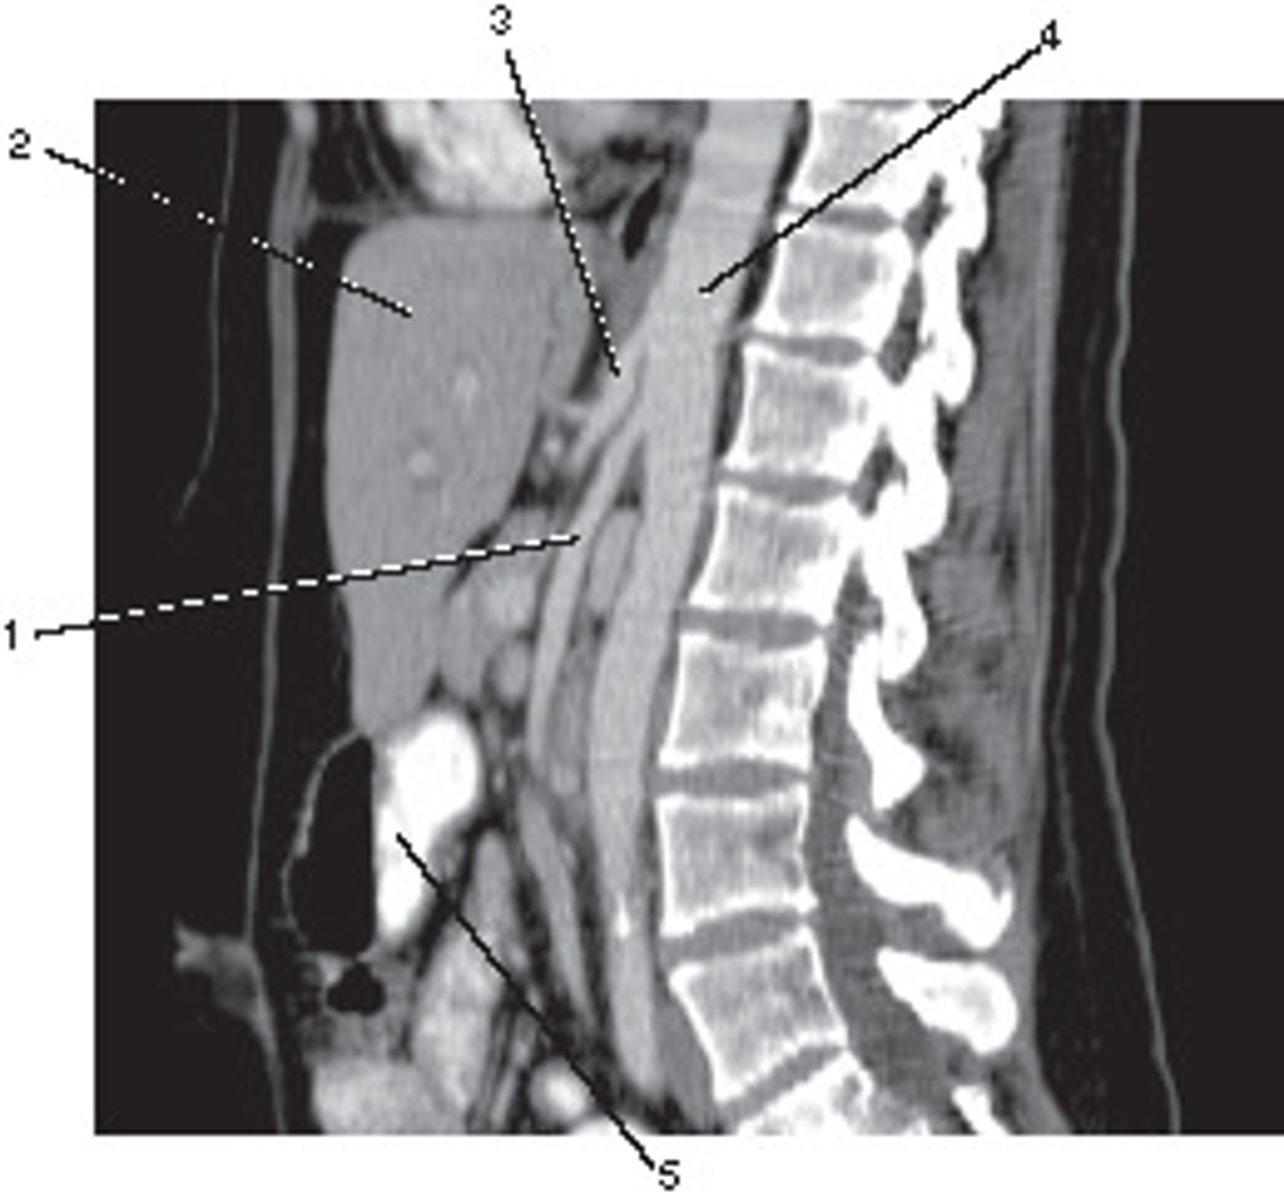

Sagittal

What anatomic plane best describes this image

<p>What anatomic plane best describes this image</p>

Descending Aorta

Number 1 corresponds to which of the following?

<p>Number 1 corresponds to which of the following?</p>

Corticomedullary;

30-40 seconds after injection,

the corticomedullary phase demonstrates optimal enhancement of the renal cortex with maximum differentiation from the renal medulla

This image of the abdomen was most likely acquired in which in which renal enhancement phase?

<p>This image of the abdomen was most likely acquired in which in which renal enhancement phase?</p>